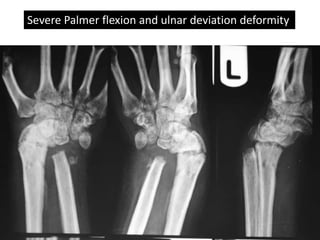

Severe Palmer flexion and ulnar deviation deformity

Severe Palmer flexionand ulnar deviation deformity